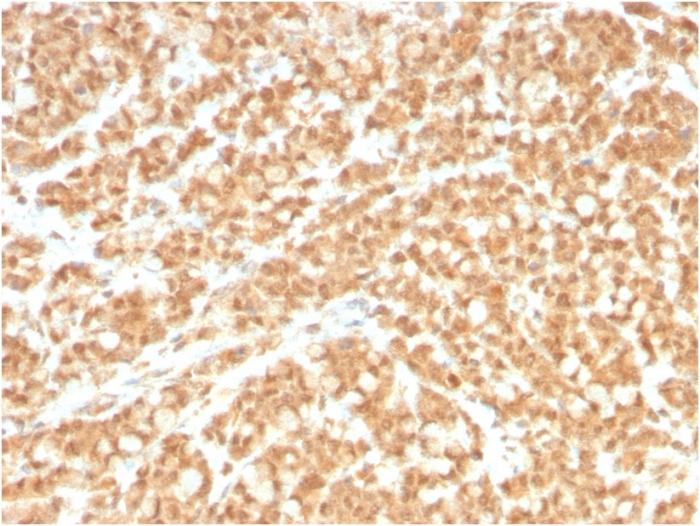

Positive Control

HL60, HuT78 and HUVEC cells. Prostate or Colon Carcinoma.

IHC, FFPE (verified)

IHC (FFPE) (verified)